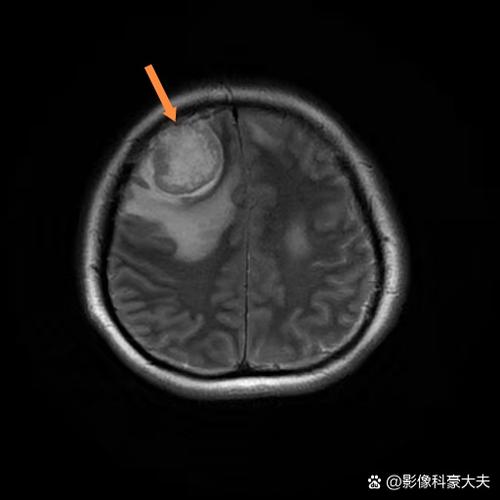

- DWI(弥散加权成像):这个序列对早期脑梗死的诊断非常敏感,但它不是导致脑梗的原因,恰恰相反,它是医生用来诊断脑梗死的工具,因为脑细胞缺血坏死后,水分子的自由运动会受到限制,在DWI图像上会显示出异常高信号,医生正是通过这个序列来发现你是否已经发生了脑梗。